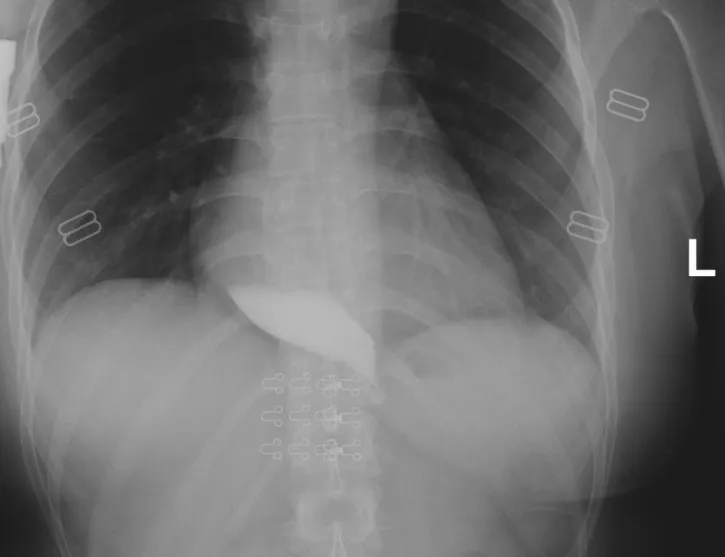

入院后,消化内科林剑兴主任详细查看了小谢的情况,在食管钡餐造影下显示,小谢食道有典型的鸟嘴征,下段狭窄,上段扩展。同时考虑到小谢还很年轻,首先要保证她未来的生活质量,但传统的药物治疗和手术治疗难以达到理想效果。